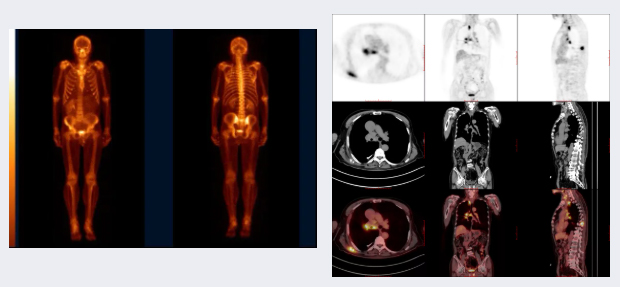

全身骨显像 / 局部骨断层融合显像

▲左为全身骨显像,右为局部骨断层融合显像

重点应用如下七个方面:转移性骨肿瘤;原发性骨肿瘤;代谢性骨病;骨感染性疾病;骨缺血性疾病;骨创伤;骨关节疾病等,结合SPECT/CT断层融合显像,能对骨病变进行精准的定位和定性诊断。